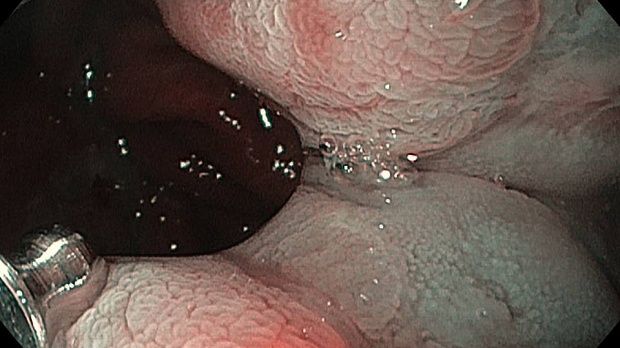

Публикации из социальных сетей: “Cobblestone esophagitis” (эзофагит со слизистой булыжной мостовой)

“Cobblestone esophagitis” (эзофагит со слизистой булыжной мостовой) - редкая эндоскопическая находка и ассоциируется с эозинофильным эзофагитом, кандидозом и пищеводом Барретта у взрослых. Он также может быть найден при тяжелом рефлюкс-эзофагите, вторичен к дистальной обструкции гастроинтестинального тракта. В нашем случае - это пациент после с 9-летним стажем бандажирования кардиального отдела желудка, признаками дуоденостаза, фундальной эрозивной гастропатией, расширением пищевода и уровнем жидкости в нем при горизонтальном положении, грыжи ПОД, эрозивно-язвенном дистальном эзофагите.. Пациент просто пришел удалить полип в прямой кишке и заодно посмотреть, что творится в желудке.... Ацетообеление+NBI+биопсия. ИПП на 3-4 мес и повтор для решения о Барретте.